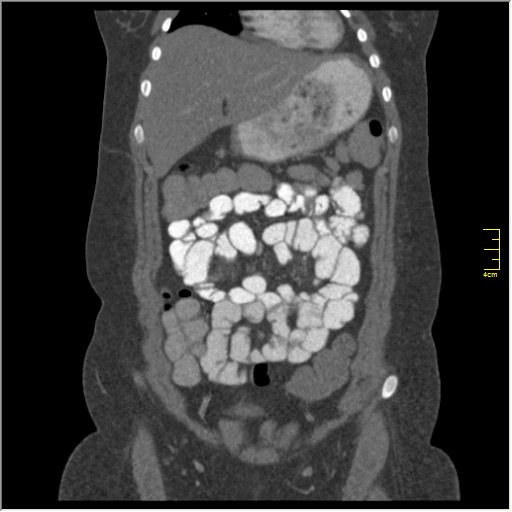

Демонстрационные изображение, оцените возможности метода! Толщина среза реконструкции 0.5-1 мм.